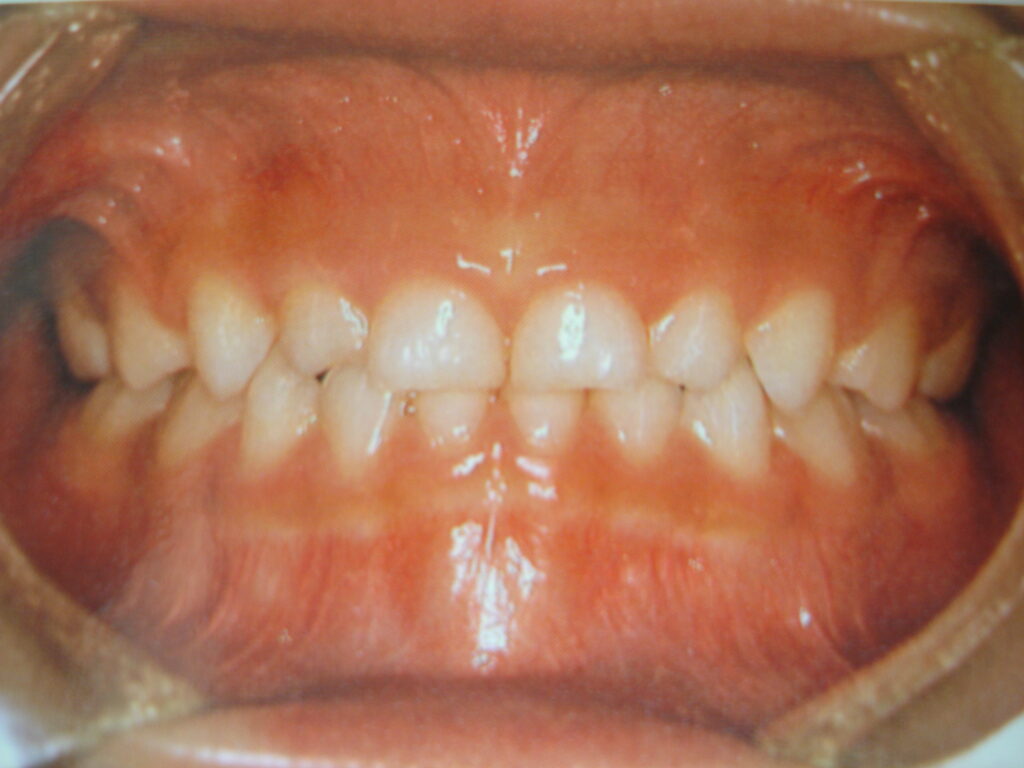

というのも実は乳歯の歯並びには正解があるのです。ではどの歯並びが正解なのか写真を見ながら確認してみましょう。

いかがですか?もしこの写真を見て「綺麗な歯並び」と思った方がいたらそれは危険です。

確かに綺麗にすき間なく並んでいますが、これは叢生になる典型的な乳歯の生え方です。

本来の正しい歯並びはすき間があることで、綺麗に並んでいるから問題ないわけではありません。